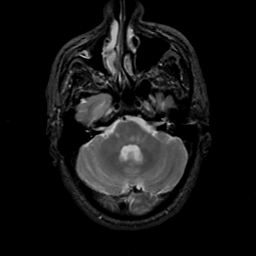

MR Study #22, December 1, 1991 -- Slice #12